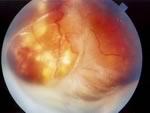

Британские ученые обнаружили, что причиной опасного наследственного глазного заболевания – семейной экссудативной витреоретинопатии – может быть мутация одного из генов. Они утверждают, что члены семей пациентов, страдающих этим заболеванием, часто сами являются носителями этой мутации, и эти люди нуждаются в методике, которая позволяла бы выявлять опасность заболевания на ранней стадии, чтобы принять необходимые меры и таким образом предотвратить потерю зрения. Обнаружен новый ген, позволяющий предотвратить развитие слепотыМеждународная группа исследователей обнаружила, что у больных семейной экссудативной витреоретинопатией – это заболевание вызывает нарушения в развитии органов зрения, что приводит к полной или частичной потере зрения – поврежден ген TSPAN12. Ученые предполагают, что обнаруженная ими генная мутация искажает клеточные сигналы, необходимые для нормального развития кровеносных сосудов, питающих сетчатку глаза. В то же время, члены семей этих больных могут быть носителями такой же генной мутации, однако симптомы заболевания у них никак не проявляются. Исследователи предполагают, что контроль наличия данной генной мутации у людей, у которых в семье уже есть такие больные, будет способствовать выявлению семейной экссудативной витреоретинопатии на ранней стадии. Тогда лечение можно будет начать еще до того, как пациент начнет терять зрение. Кроме того, ученые считают, что полученные ими результаты будут способствовать лучшему пониманию природы других, более распространенных, глазных заболеваний, которые ведут к потере зрения. Доктор Кармел Тумс (Carmel Toomes) из Института молекулярной медицины в Лидсе, Великобритания, сказал: «Это открытие поможет нам по-другому вести лечение и консультирование наших больных. Теперь мы сможем выявлять людей, которые являются носителями обнаруженной генной мутации, и начинать лечение до того, как у них появятся какие-либо изменения в сетчатке глаза. Это резко снижает вероятность того, что такой пациент ослепнет, потому что если это заболевание будет обнаружено на ранней стадии, зрение больного можно будет спасти при помощи хирургического вмешательства». В исследовании приняли участие 70 больных семейной экссудативной витреоретинопатией. Мутация гена TSPAN12 была обнаружена у каждого десятого из них.

Американские ученые обнаружили ранее неизвестное наследственное заболевание сетчатки глаза. Отчет об исследовании группы специалистов из Университета Айовы под руководством Винита Махаяна. По словам Махаяна, симптомы заболевания обусловлены пороком развития сосудов желтого пятна сетчатки (область наибольшей остроты зрения). В результате кровотечений на сетчатке образуются кисты и рубцы, что приводит к частичному выпадению или помутнению полей зрения у больного. Ученым удалось открыть новую болезнь после того, как они обследовали 17 человек в возрасте от 5 до 64 лет, представляющих три поколения одной семьи. Различные нарушения зрения были выявлены у каждого из родственников, в основном это было ослабление зрения, не связанное с близорукостью или дальнозоркостью (ослабление зрения) и косоглазие. У семи членов семьи исследователи обнаружили множественные выросты (кисты) в центре желтого пятна, а также плоские, округлые участки усиленной пигментации по всей поверхности сетчатки, пишет "EUROLAB". Выявленная группой Махаяна семья пока что является единственной известной науке группой носителей дефектного гена. Ученые из Айовы намерены разыскать других больных с данной аномалией. На основании анализа родственных связей уже известных пациентов, офтальмологи сделали вывод о том, что болезнь наследуется по аутосомно-доминантному типу. Когда гены, вызывающие новое заболевание, будут найдены в хромосомах больных людей, у врачей-клиницистов появится возможность обследовать потомство носителей дефекта, не допуская передачи мутации следующим поколениям. Генетическое обследование даст возможность устанавливать вероятность развития слепоты еще у плода в утробе матери или даже у эмбриона в пробирке при искусственном оплодотворении. Кроме того, можно будет обследовать всех родственников больных людей, чтобы определить, насколько с течением лет у них вероятно развитие тяжелых форм новой глазной болезни.